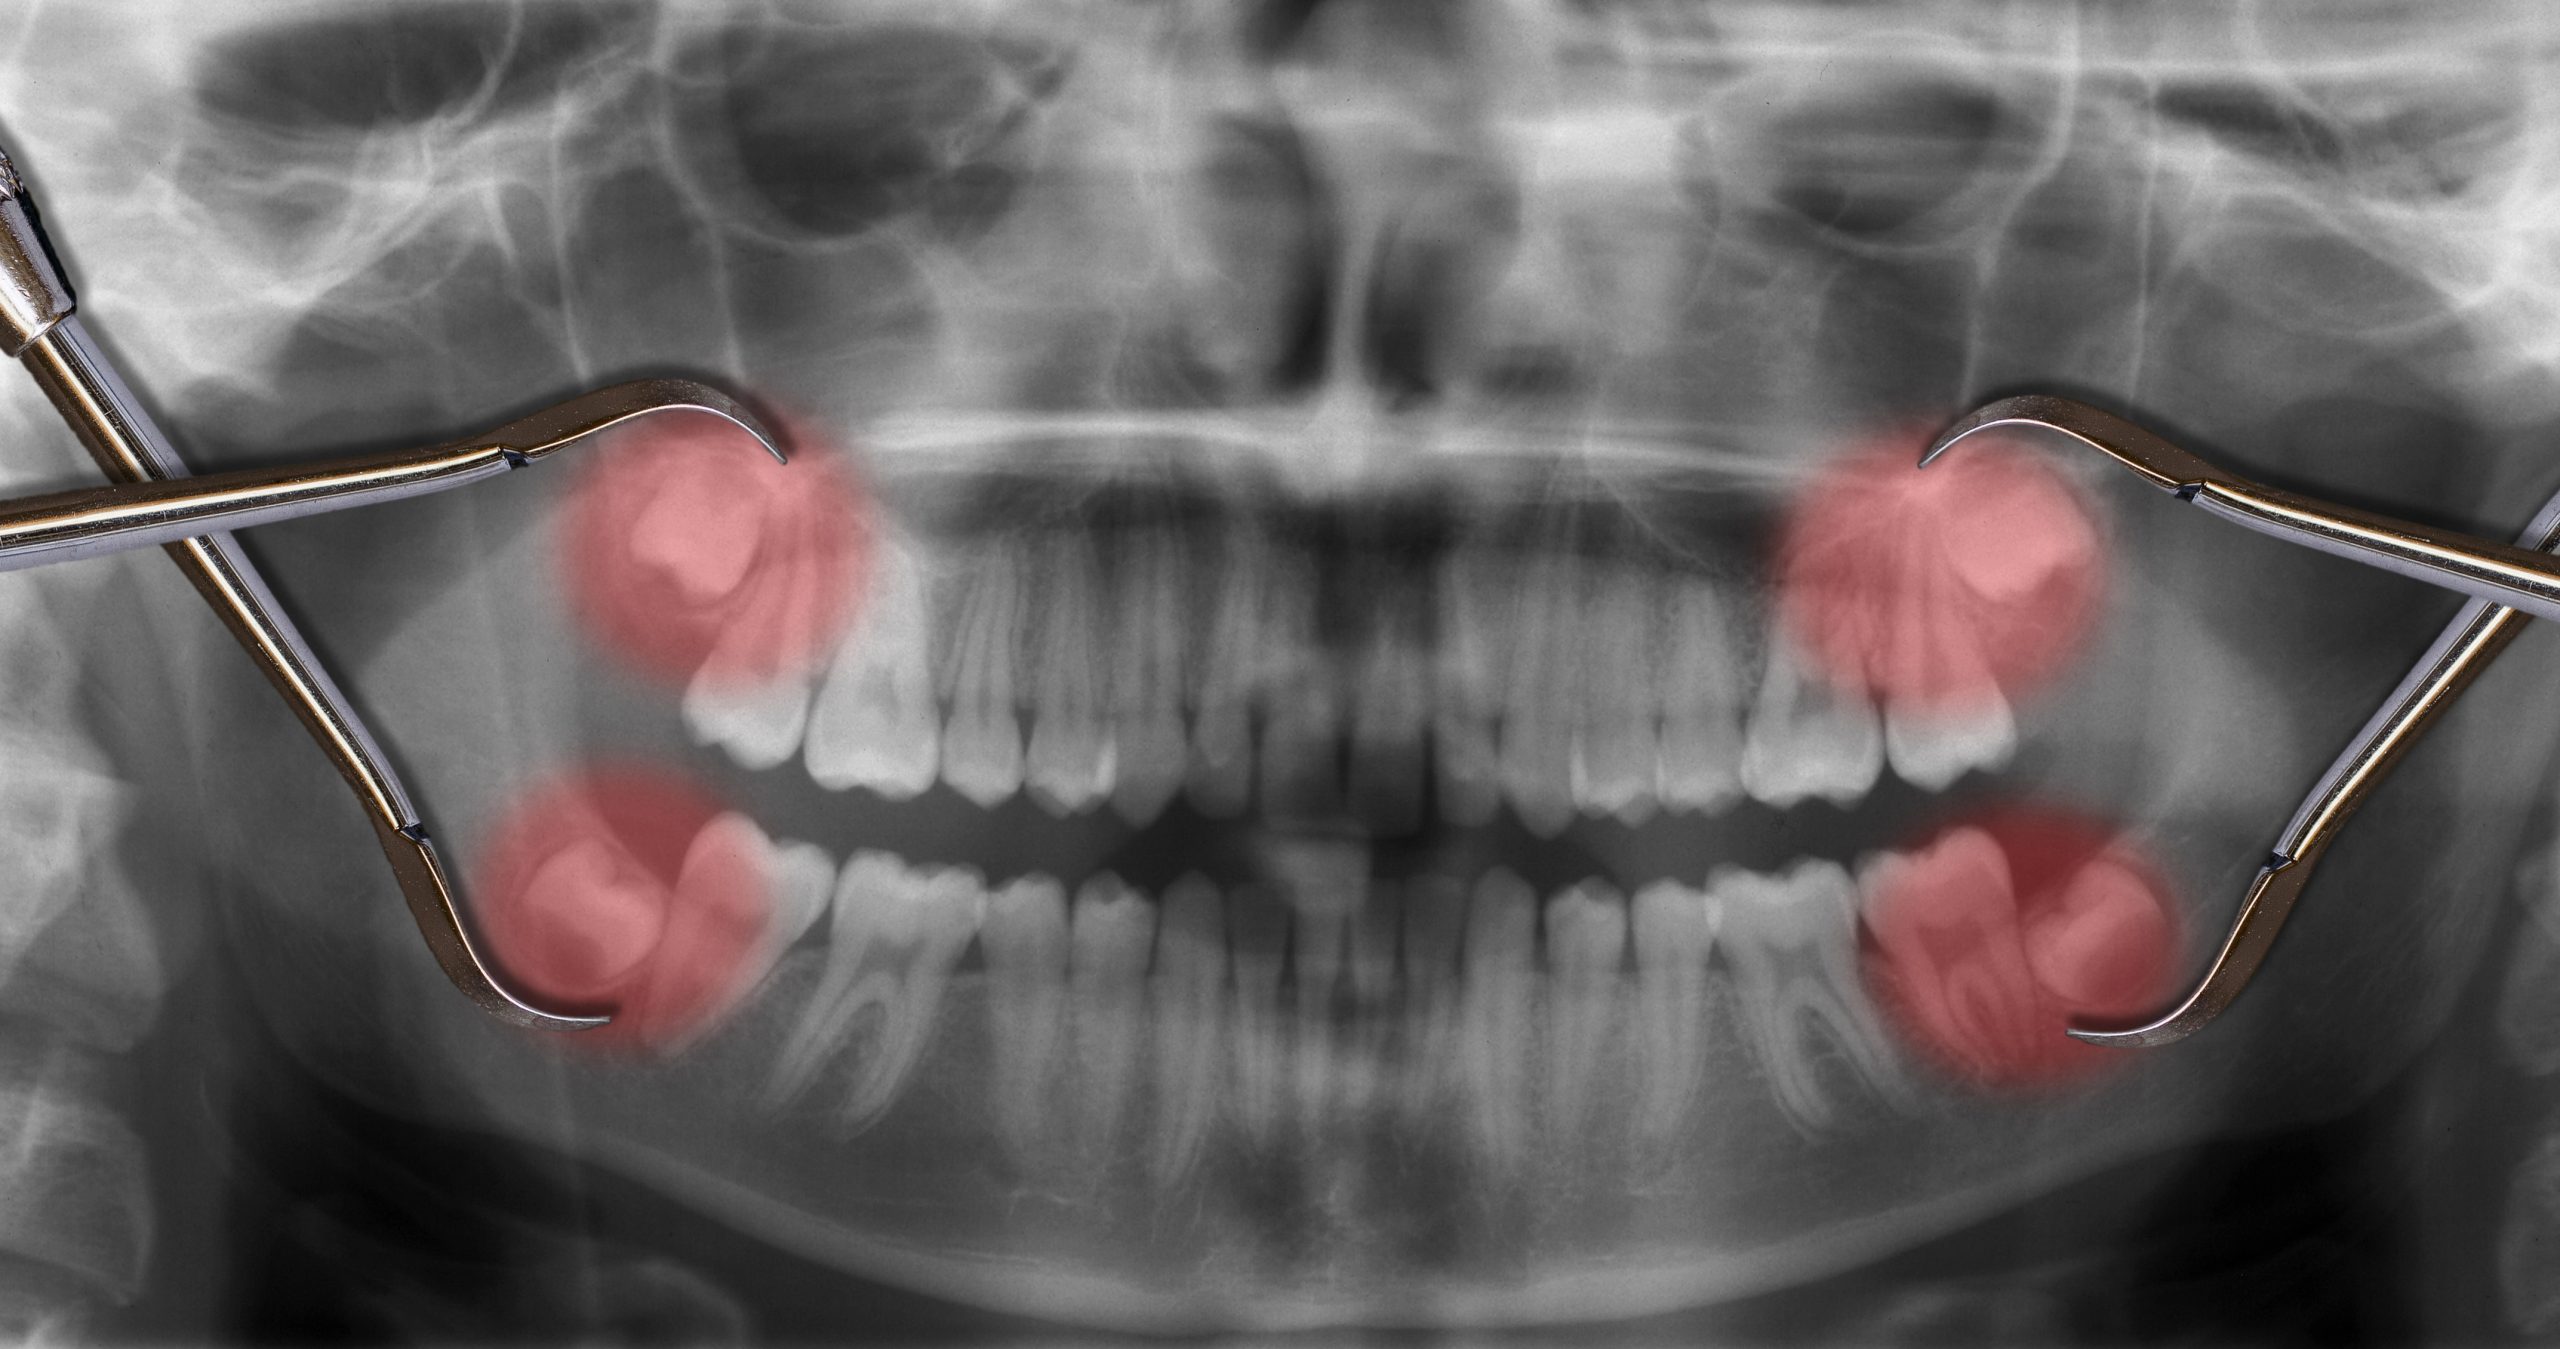

Wisdom teeth usually develop and erupt in the late teens or early adulthood. While some people can accommodate these “third” molars without complications, many experience problems due to insufficient jaw space or improper eruption angles. When wisdom teeth get stuck and infected, extraction is the recommended treatment.

Teeth that get stuck before or during eruption are referred to as being impacted. These impacted wisdom teeth can cause damage to adjacent teeth, affect your bite (how your teeth come together), and become infected.

Downtown Toronto wisdom tooth extraction is a necessary intervention. It involves the surgical removal of one or more of your third molars to prevent or resolve these complications. In many cases, we can detect problems before symptoms occur. But if there is significant time between dental checkups and X-rays, you might not know about your wisdom teeth problems until pain or infection occurs.

• Cyst Formation: Though less common, impacted wisdom teeth can sometimes lead to cysts within the jawbone, visible on X-rays.